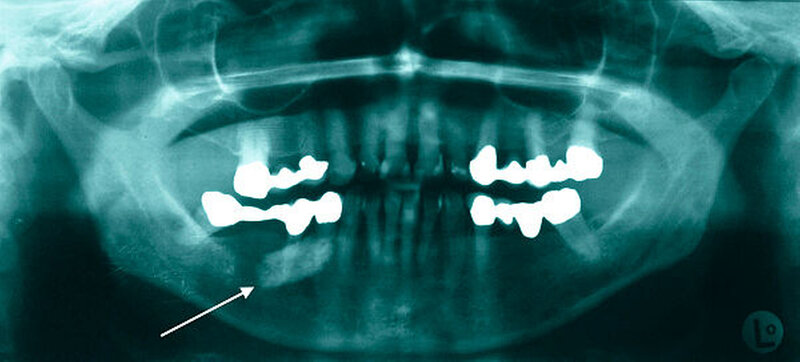

Aufgrund des ausgeprägten Lokalbefunds (Abbildung 2) konnte die Verdachtsdiagnose klinisch durch die bimanuelle Palpation des Mundbodens bestätigt werden. Die Bildgebung mittels Sonografie komplettierte das diagnostische Procedere (Abbildung 3). Nebenbefundlich nahm die Patientin aufgrund von anamnestisch rezidivierenden, tiefen Beinvenenthrombosen Rivaroxaban (Xarelto®, 20 mg, 1–0–0) zur Antikoagulation ein.

Bei klinischem, sonografischem und radiologischem Verdacht auf einen im Ausführungsgang der Glandula submandibularis rechts gelegenen und im hinteren Mundboden lokalisierten Speichelstein, erfolgte nach ausführlicher Aufklärung der Patientin die operative Steinentfernung.

Neben der klinischen bimanuellen Tastuntersuchung des Mundbodens beinhaltet die traditionelle diagnostische Vorgehensweise die Sonografie als Goldstandard [Yoshimura et al., 1989] sowie die Röntgenbildgebung zur genauen Lokalisationsbestimmung bei unklaren Befunden [Yoshimura et al., 1989; Yuasa et al., 1997; Iro und Zenk, 2003; Capaccio et al., 2007]. Die früher regelmäßig durchgeführte Sialografie ist im Zeitalter der hochauflösenden Sonografie in den Hintergrund geraten und wird nur noch in Ausnahmefällen durchgeführt.

Goldstandard der Bildgebung bei Sialolithiasis der Gl. submandibularis ist die Sonografie. Bei unklarem Befund sollte eine röntgenologische Bildgebung erfolgen.